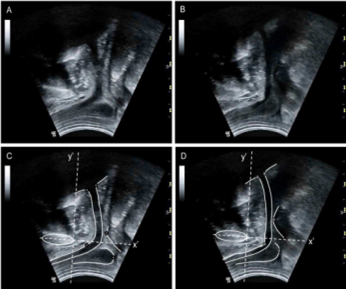

临床肌骨超声可针对性的进行神经、血管、韧带、肌肉、筋膜甚至半月板等骨关节结构的动态的直观观察,在肌骨超声的引导下,可客观准确的定位病灶并进行有效的处理。

科室目前已经全面开展了超声定位下的富血小板血浆注射技术(PRP)、局部封闭注射技术、高渗葡萄糖注射增生疗法、神经水分离治疗技术等。